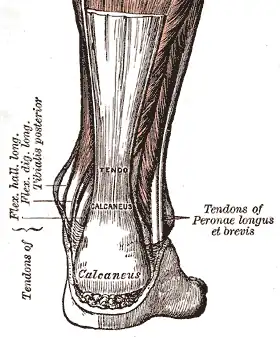

Le tendon calcanéen (ou tendon d'Achille) est un tendon du membre inférieur qui sert d'insertion au muscle triceps sural sur le calcanéus.

Le tendon calcanéen nait de la fusion, au niveau du tiers inférieur de la jambe.des lames tendineuses terminales des muscles gastrocnémien et soléaire, constituant le muscle triceps sural. Il est rejoint et fusionne parfois avec le tendon terminal du muscle plantaire.

Il s'insère sur le tubercule du calcanéum.

C'est un tendon plat et puissant. Il mesure de 12 à 15 cm de long pour une épaisseur de 5 à 6 mm. C'est le tendon le plus volumineux du corps humain[2].